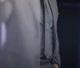

Figura 20. Caso clínico tratado mediante injerto óseo de lámina autóloga. A) Situación clínica basal de la atrofia del segundo cuadrante. Vista lateral. B) Situación clínica basal de la atrofia del segundo cuadrante. Vista oclusal. C) Situación clínica basal de la atrofia del segundo cuadrante. Vista vestibular.

Figura 21. Caso clínico tratado mediante injerto óseo de lámina autóloga. Continuación. A) Obtención del injerto óseo autólogo de la rama mandibular. B) Lámina de injerto óseo autólogo. C) Posicionamiento de la lámina oclusal en la dirección que será fijada bajo el colgajo tunelizado. D) Fijación de las láminas oclusal y vestibular a través del diseño de colgajo tunelizado.